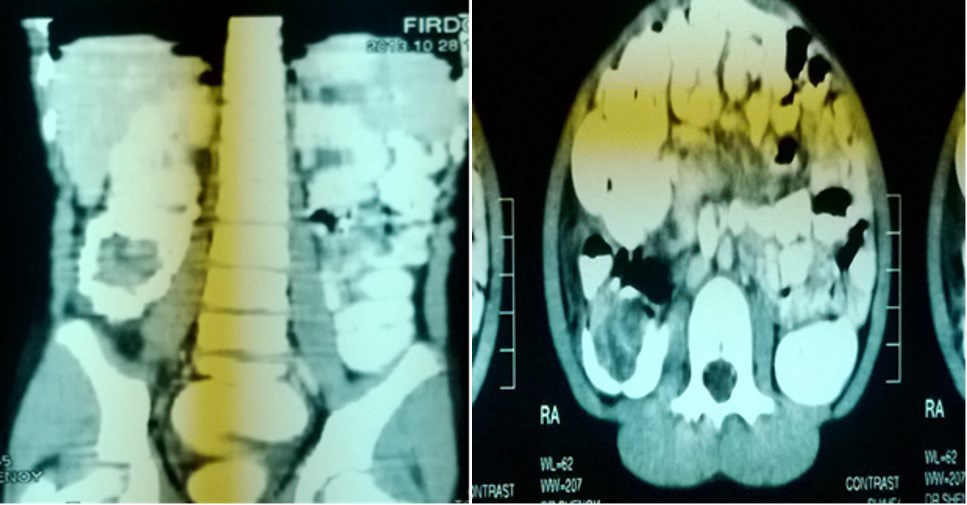

Computer tomograpahy:

• CT was done in 2 of our cases

• 1 case of PEUTZ JEGHERS SYNDROME

• 1 case was of chronic intussusception with benign polyp as lead point in ascending colon

Chronic intussusception:

• 12 years old female patient presented with chronic abdominal pain since 6 months.

• USG ABDOMEN-WNL.

• CT ABDOMEN.